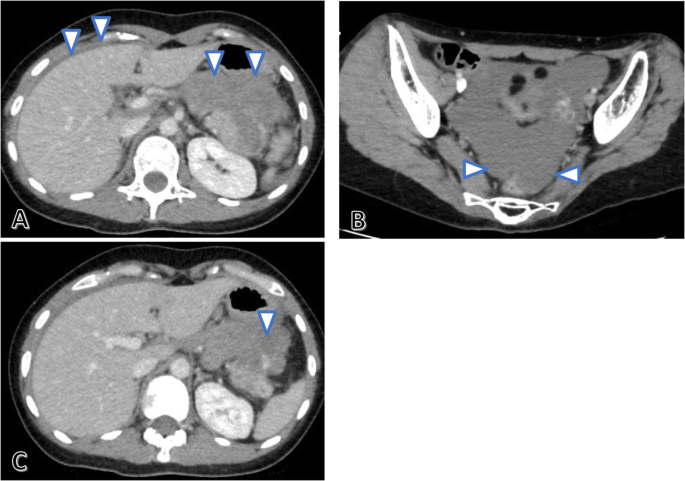

Contrast-enhanced abdominal CT performed in the emergency department revealed ascites with high CT values in the liver surface and pelvis (Fig. 2a, b), and leakage of contrast medium in the anterior of the pancreatic tail tumor to the omental bursa (Fig. 2c). The diagnosis was intra-abdominal hemorrhage due to a ruptured metastatic pancreatic tail tumor, and an urgent distal pancreatectomy was, therefore, performed.

Contrast-enhanced abdominal computed tomography (CT) conducted in the emergency department. Ascites with high CT values (arrow) is observed on the liver surface (a) and in the pelvis (b). Leakage of contrast medium (arrow) is observed from the anterior of the pancreatic tail tumor to the omental bursa (c)